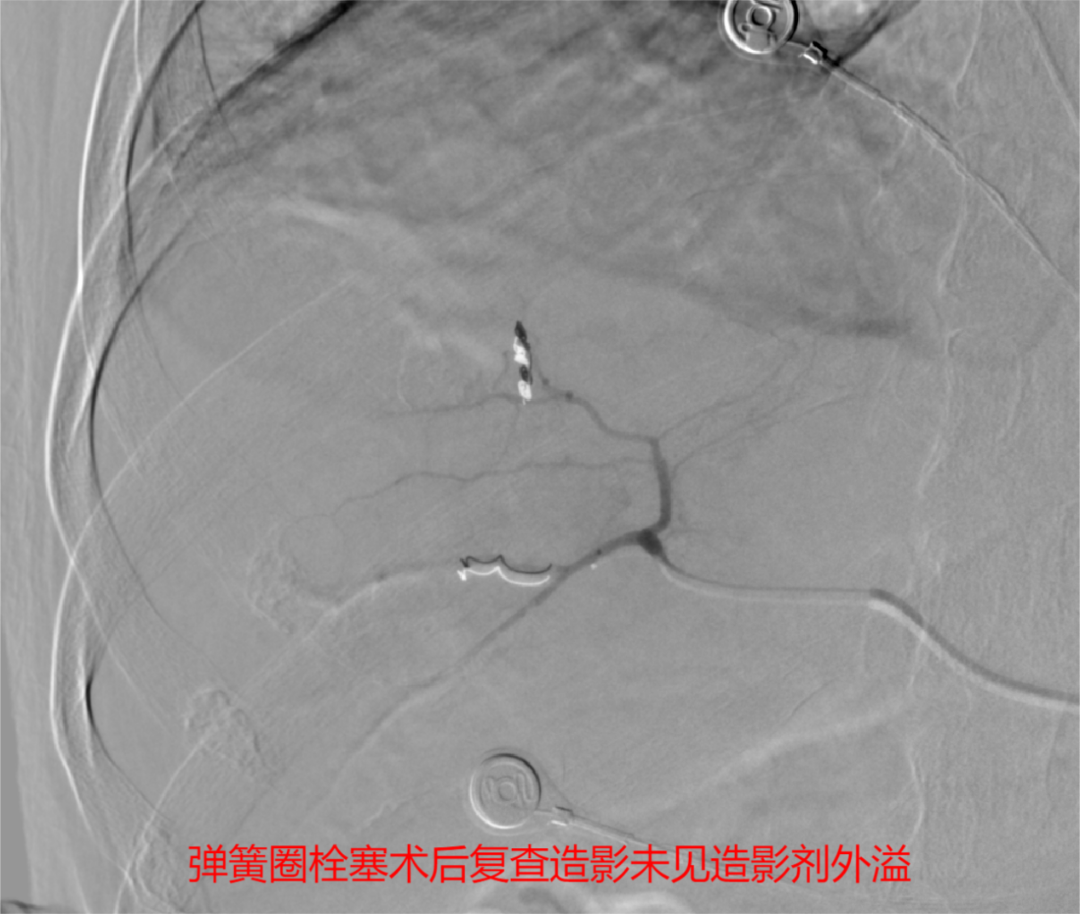

肝脏破裂介入治疗无需全麻,仅通过约1毫米的血管穿刺点进行血管内操作,在DSA下寻找出血点,用栓塞材料“堵”住止血点即可,可在短时间内达到快速止血、抢救病人生命的同时,大大减少血液制品的需求。这种新型的微创介入手术既可以及时抢救生命,又可以大大降低手术风险,减少并发症。时间就是生命,在征得患方同意后,介入团队迅速为患者实施手术抢救。近一个小时的手术,精准地将栓塞材料堵住出血点,成功挽救了患者的生命,提高了患者的生存质量,为患者的后续治疗赢得了机会。

(2)动脉栓塞治疗:①肝损伤部位和拟栓塞的靶血管确定后,超选择性插入相关动脉主干近端,将明胶海绵根据需要剪成粗细不同的颗粒[直径1mmX(1~3mm)]或条块(lmm lmmX5mm),装入混有造影剂及庆大霉素的注射器内并摇匀,在透视监控下缓慢、少量、分次注入损伤血管,当血管血流明显缓慢或铸形,提示出血动脉已闭塞,再造影复查见造影剂外溢消失。